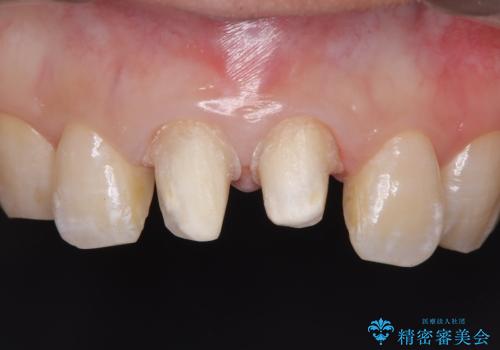

前歯の根のところに違和感がある|根尖性歯周炎|精密根管治療|オールセラミッククラウン|見た目も改善

- 前歯の違和感を主訴にご来院された患者様です。

根尖性歯周炎に罹患し根の先に膿が溜まっているのが原因でした。

精密根管治療後、オールセラミッククラウンで治療を行いました。